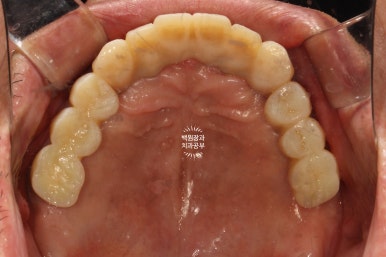

그리하여 완성된 최종보철물입니다!!

옛날부터 임플란트 틀니용으로 사용하시던 임플란트 3개는 임플란트 주위염이 조금 있어 약~간 쇠기둥 색깔이 보인다는 단점이 있긴 하지만, 다른 임플란트들은 꽤나 예쁘게 제작이 되었네요.

위 아래 교합면 사진을 보시면, 과연 이게 임플란트인가? 싶으실거에요. 치아에 지르코니아 크라운을 붙인 것과 큰 차이를 못느낄 정도로 정말 자기 치아같이 예쁘게 제작된 임플란트 크라운을 보실 수 있습니다!!